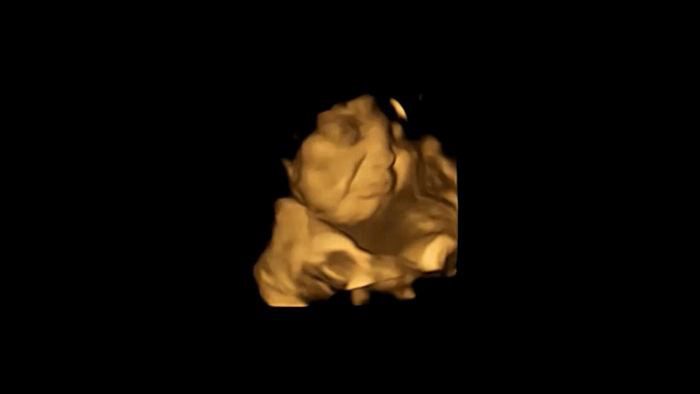

Zespół naukowców przeprowadził następnie analizę poklatkową ruchów twarzy płodów. Wyniki pokazały, że płody, których matkom podano kapsułkę z marchwią, uśmiechały się.

Wyraz twarzy płodu po zjedzeniu przez mamę marchwi

Wyraz twarzy płodu po zjedzeniu przez mamę marchwi © FETAP | Durham University